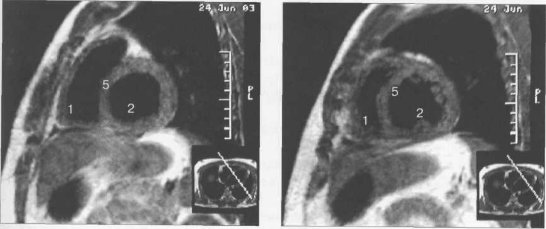

Рис. 9.47. МРТ сердца. Аксиальная плоскость.

Здесь и на рис. 9.48—9.52:

I — правый желудочек, 2 — левый желудочек, 3 — правое предсердие, 4 — левое предсердие, 5 — межжелудочковая перегородка, 6 — межпредсердная перегородка, 7 — задняя стенка левого желудочка, 8 — восходящая часть аорты, 9 — дуга аорты, 10 — нисходящая часть аорты, 11 — легочный ствол, 12 — правая легочная артерия. 13 — левая легочная артерия, 14 — верхняя полая вена, 15 — нижняя полая вена, 16 — трахея.

Рис. 9.52. МРТ сердца. Четырехкамерные сечения.

На рис. 9.47—9.52 представлены Т1-ВИ наиболее часто используемых МР-сечений сердца.